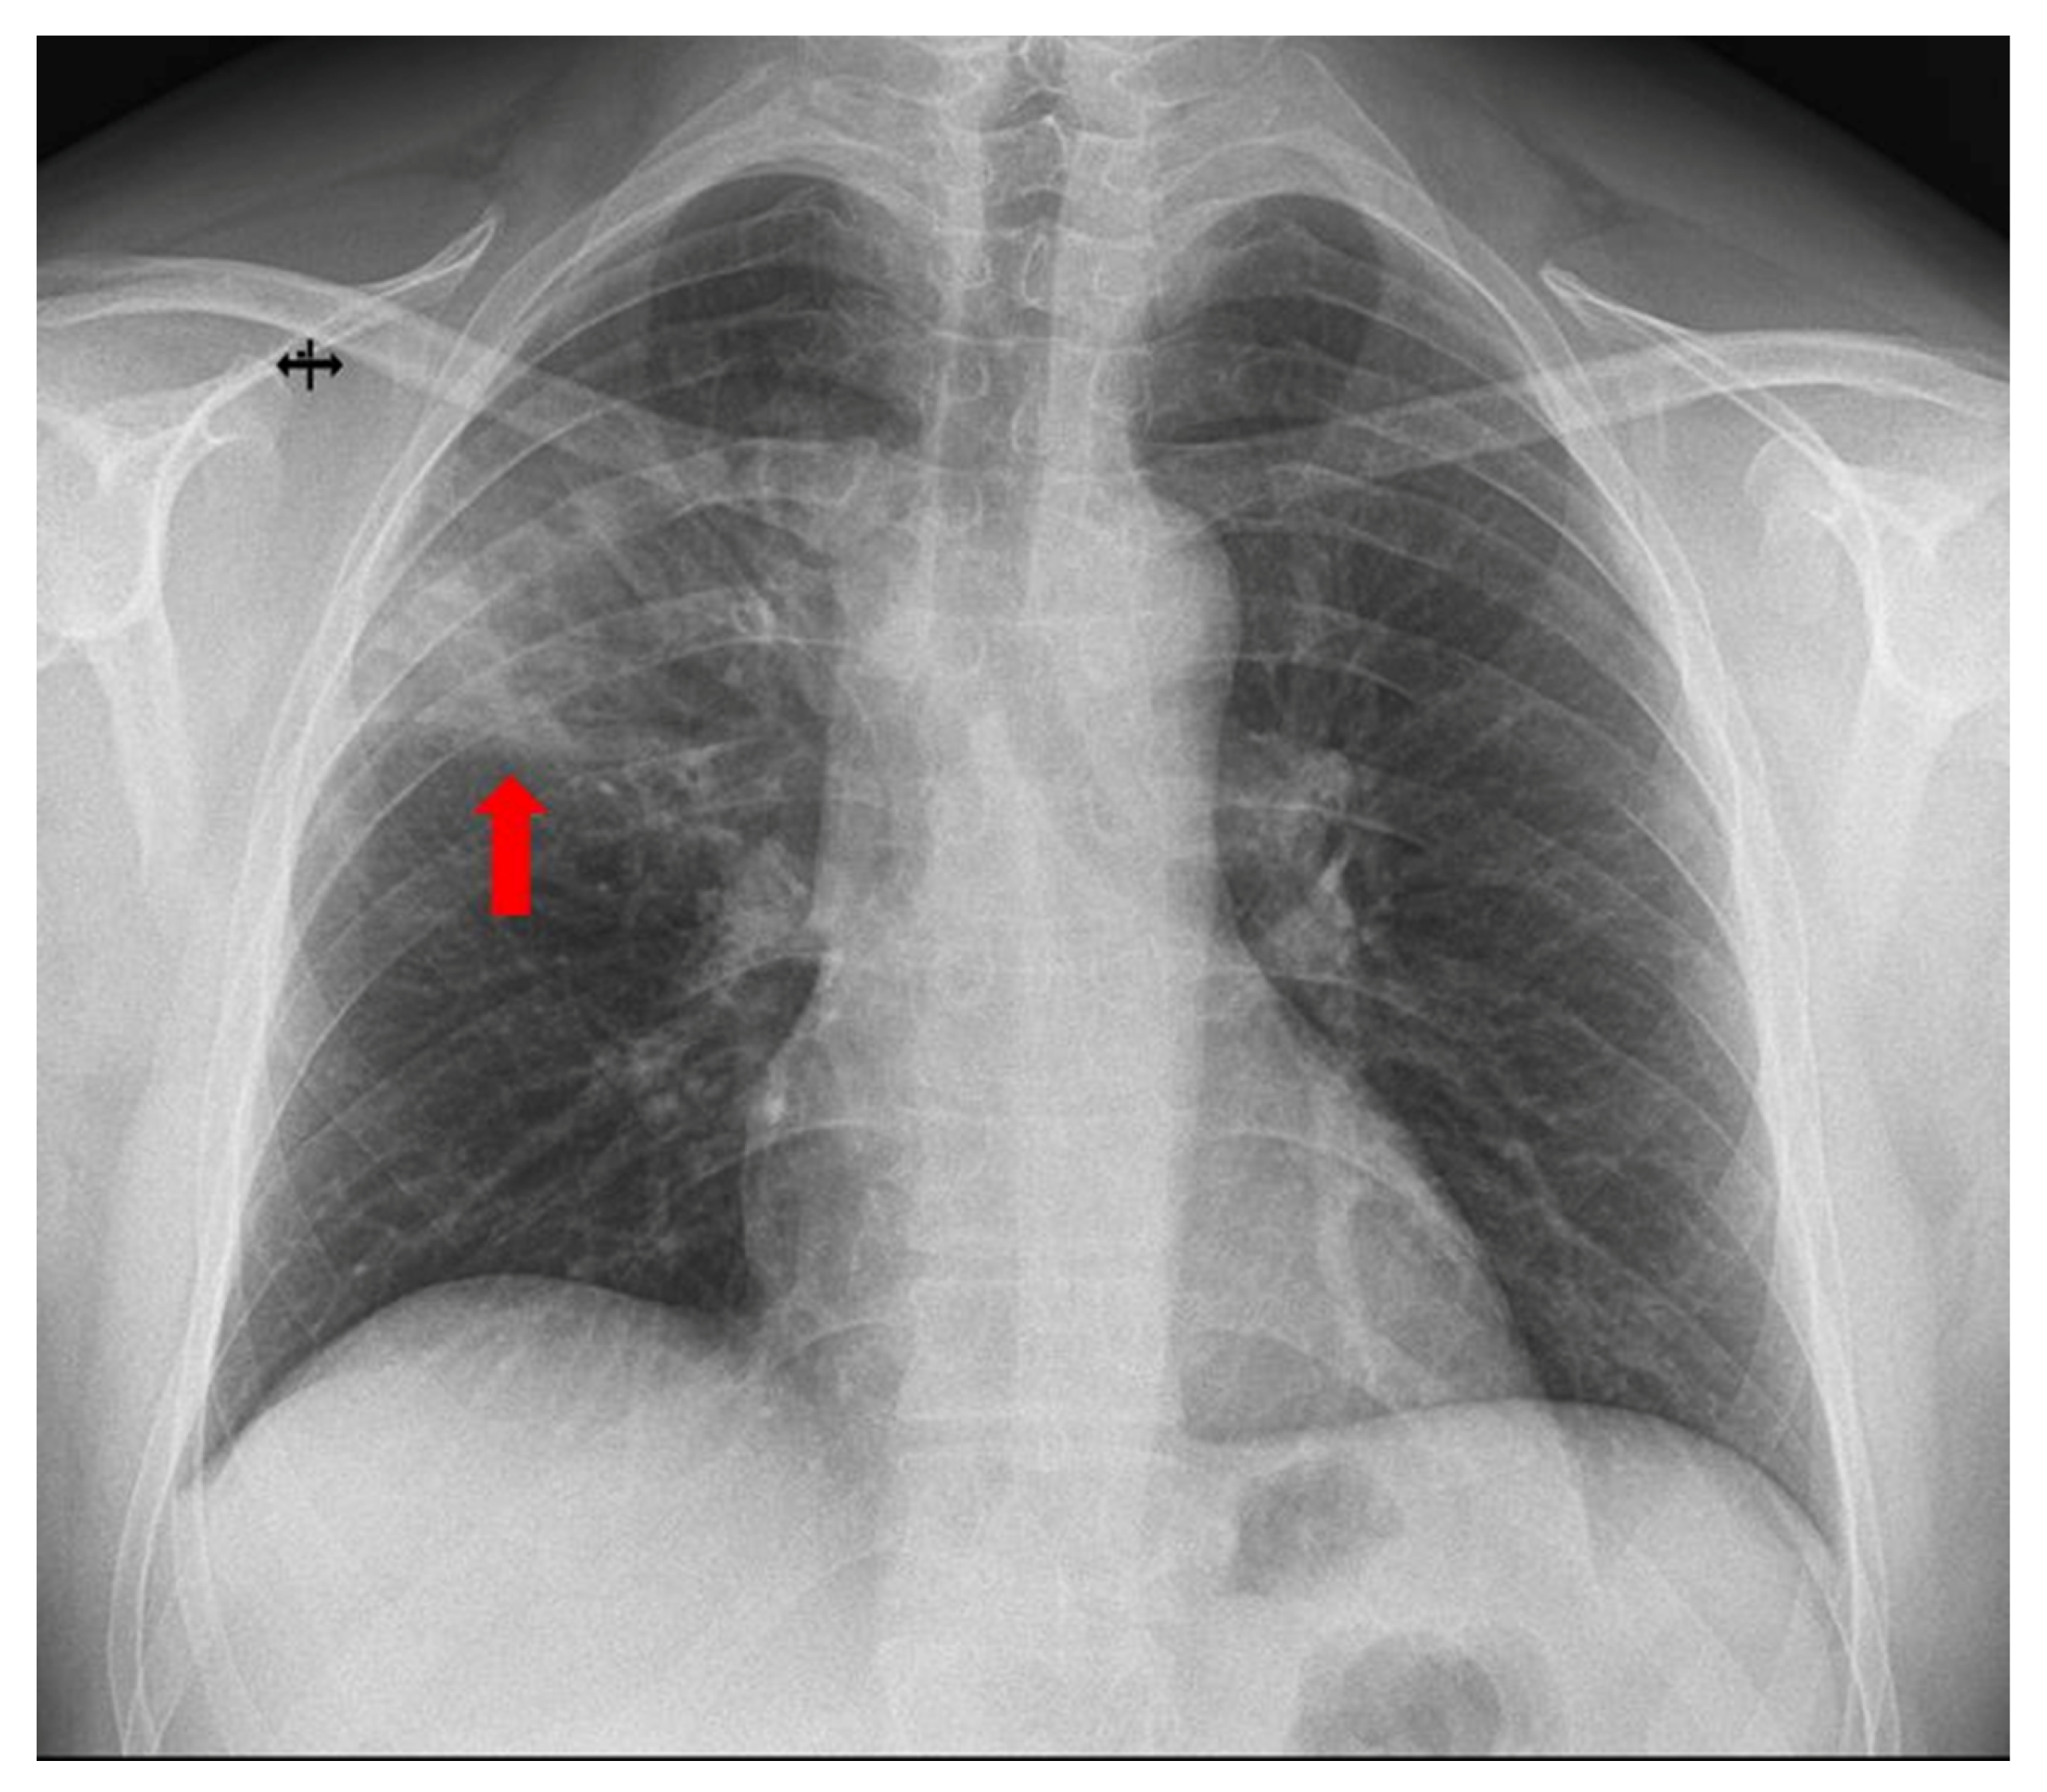

Figure 1. A 42-year-old non-smoking male electrician with occupational exposure to respiratory irritants presented to the emergency department with a 24 h history of fever (38.7 °C), non-productive, irritating cough, and diffuse post-tussive chest pain. His past medical history included SARS-CoV-2 infection four years earlier and mixed dyslipidemia controlled with statins and fenofibrate. On admission, he was febrile (38.7 °C), normotensive, and maintained normal oxygen saturation. Lung auscultation revealed bilateral vesicular breath sounds without additional adventitious sounds. Laboratory evaluation demonstrated an inflammatory response (elevated C-reactive protein—108 mg/L (0–5 mg/L) and procalcitonin—0.17 ng/mL (0–0.05 ng/mL)), with normal value of leukocytes (WBC—9.99 × 103/µL, neutrophils—6.86 × 103/µL, lymphocytes—1.82 × 103/µL), and hypertriglyceridemia. Chest X-ray revealed a subpleural, pseudo-triangular opacity of inhomogeneous density in the upper third of the right lung field (red arrow). For further evaluation of the radiographic abnormality and pulmonary function, spirometry with bronchodilator testing and thoracic CT were recommended.